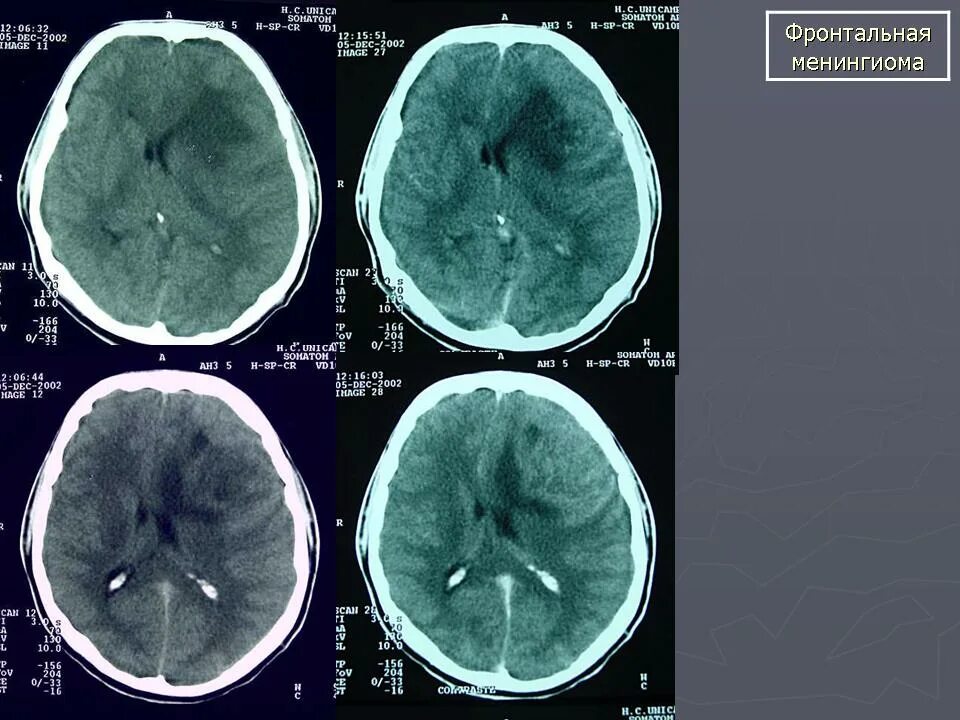

Менингиомы головного мозга мкб